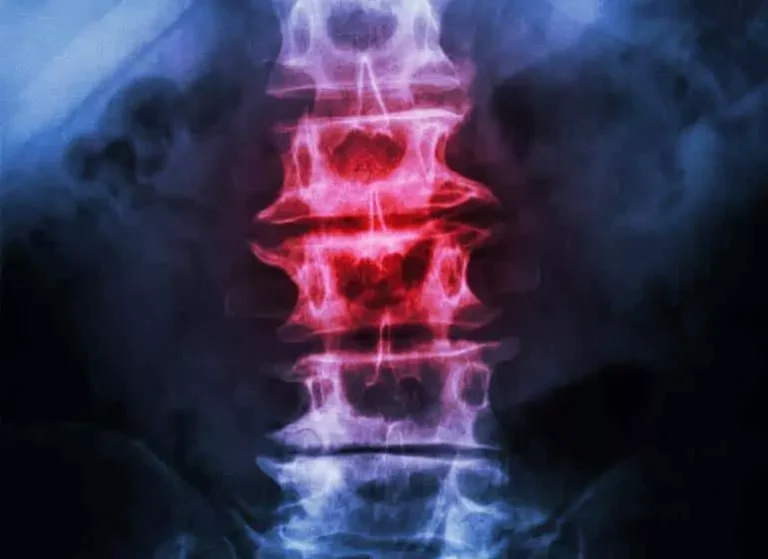

An X-ray image showing a spine with a section in red.

Spodylosis

Spondylosis

Thankfully most folks dealing with spondylosis, or spinal osteoarthritis, don’t require surgery and there are plenty of alternative treatments to investigate like acupuncture, short-term bed rest, and other lifestyle modifications. We help with adjustments, massage, and physical and occupational therapy modalities.

Learn more about Spondylosis.